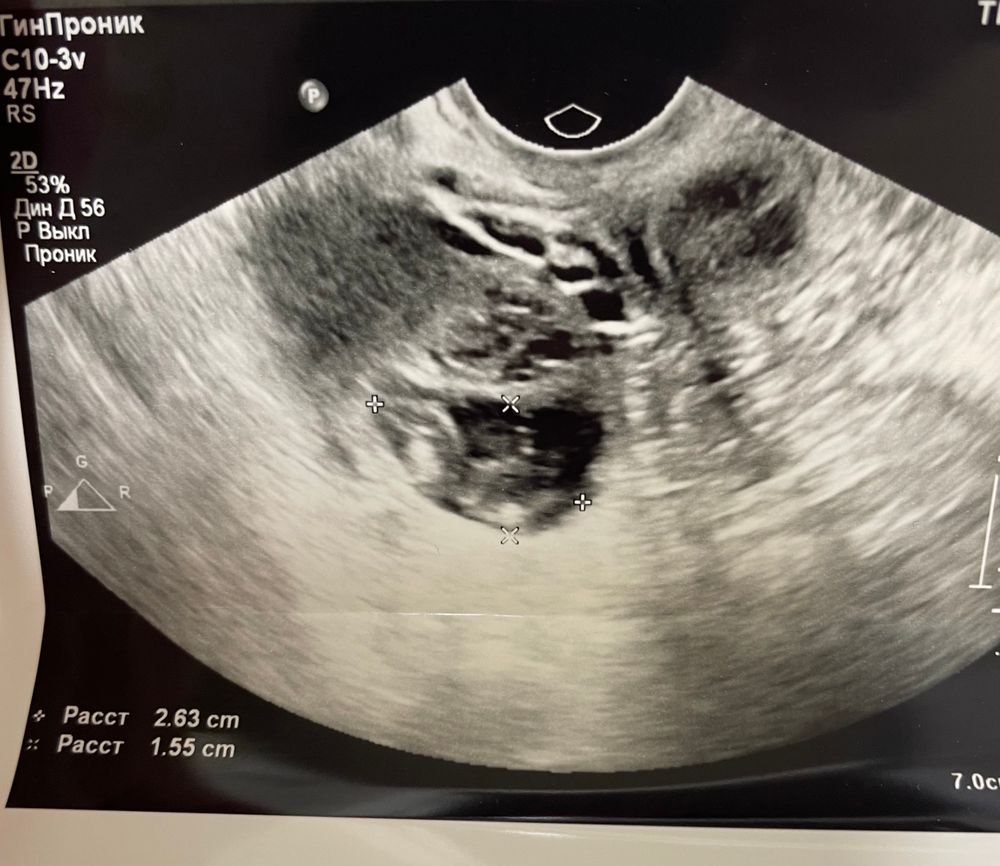

По УЗИ жёлтое тело отличается от фолликула размытыми краями и наличием кровотока. Тут края нечёткие, так что это скорее всего и правда ЖТ, наверное с прошлого цикла.

По узи форма похожа на жт, размер хороший. Про эндометрий вам что написали? Про жидкость (хотя на 5-6 дпо уже может не быть её)?

Катерина, я ходила по договоренности, больше интересовало есть ЖТ или нет. Она мне его показала на мониторе, сказала размеры. Про эндометрий и жидкость ничего не сказала. Но в заключении написано: эндометрий 17, жидкости нет. Поэтому не могу даже сказать, это реальное заключение или просто приписка для гинеколога 🤷🏻‍♀️ Но сказала, что все очень хорошо, и очень хорошее ЖТ

Елена, не нравится размер( начиталась, что больше 22мм это уже киста (больше беспокоит не киста ЖТ, а - фолликулярная) все пытаюсь понять есть у меня овуляция или нет